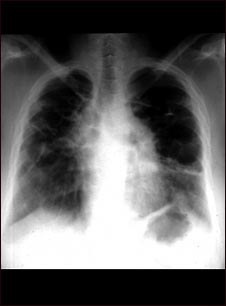

Sarcoide, etapa IV; rayos X de tórax

La placa muestra un sarcoide avanzado, cicatrización de los pulmones (bandas claras) y la formación de cavidades (áreas oscuras en la parte superior derecha).